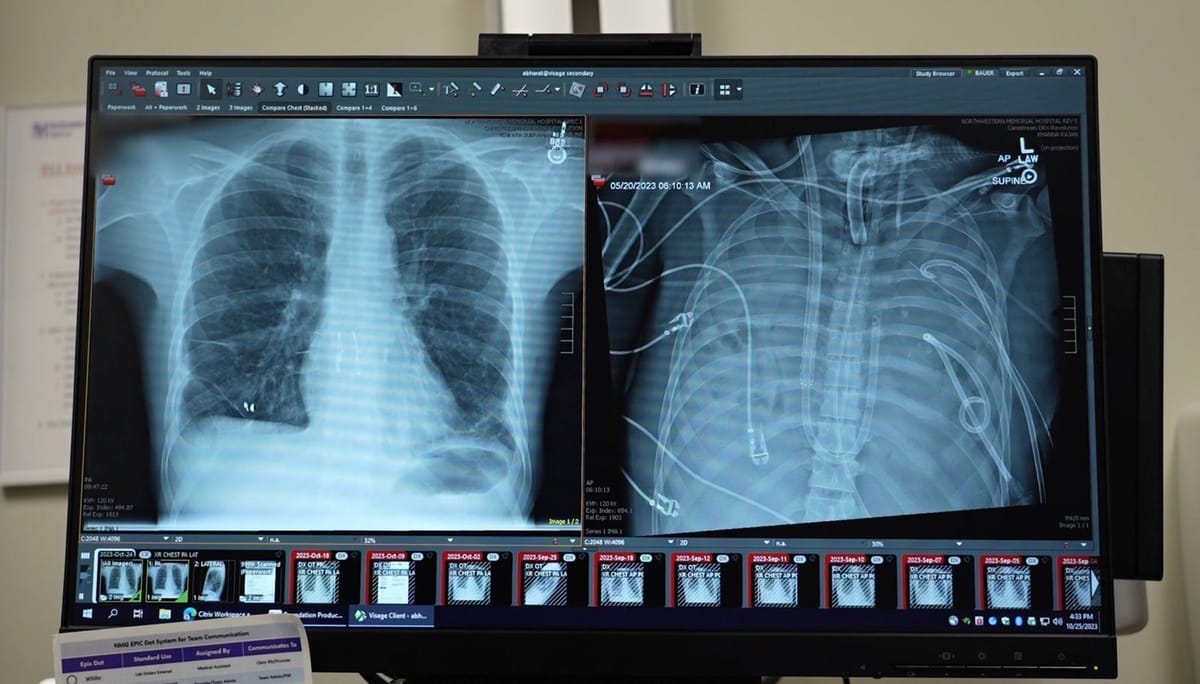

The patient, treated by a team led by thoracic surgeon Ankit Bharat at Northwestern University, was critically ill when he arrived at hospital. His heart stopped shortly after admission, and doctors were forced to perform CPR.

To overcome this, the surgical team created an artificial lung system that temporarily took over the lungs’ role. The system oxygenated the blood, removed carbon dioxide, and maintained stable circulation, allowing the patient to survive without lungs at all.

After the diseased lungs were removed, the patient’s condition began to improve.

His blood pressure stabilised, organ function recovered, and the infection reduced. Two days later, donor lungs became available, and surgeons successfully carried out a double lung transplant. More than two years on, the patient has returned to normal daily life with healthy lung function.